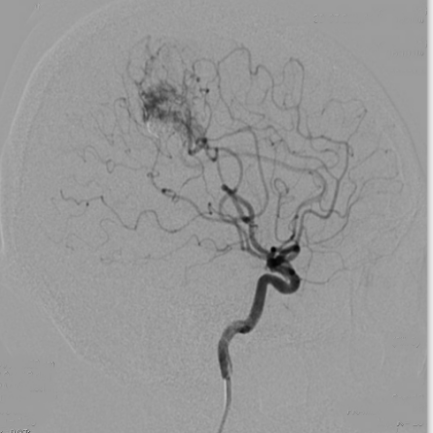

为了观察动静脉畸形的栓塞效果,术后行DSA造影。DSA造影显示畸形团基本消失,栓塞效果较好